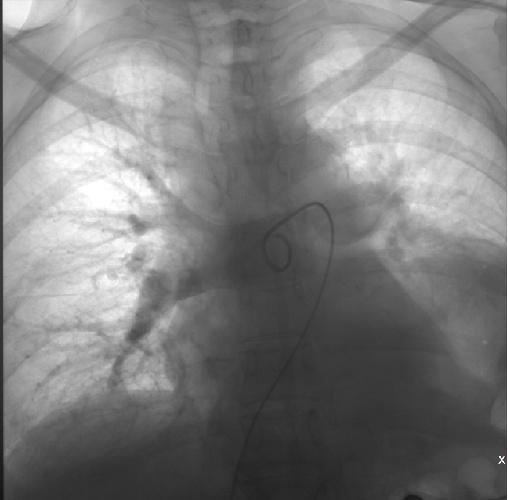

消毒、穿刺、置管、造影、血栓抽吸系统置入.....介入科尚鸣异主任和助手殷响医生在台上分秒必争,默契配合。随着机器有节奏地运转,致命的血栓被逐渐粉碎,并抽吸出体外。一小时后手术顺利完成,复查肺动脉造影显示右肺动脉血栓消失, 血管轮廓正常,管腔也粗了。于阿姨全程清醒,无明显不适。她心里清楚,自己刚刚与死神擦肩而过。术后,于阿姨的脉搏氧饱和度逐渐上升、血压趋于平稳,血气分析结果逐步好转。目前在接受下一步的积极治疗中。

术中造影可见右肺动脉干充盈缺损,

轮廓僵硬,管腔狭窄

导管头顶入血栓中

术后复查造影可见右肺动脉血栓消失,

轮廓正常,管腔也粗了